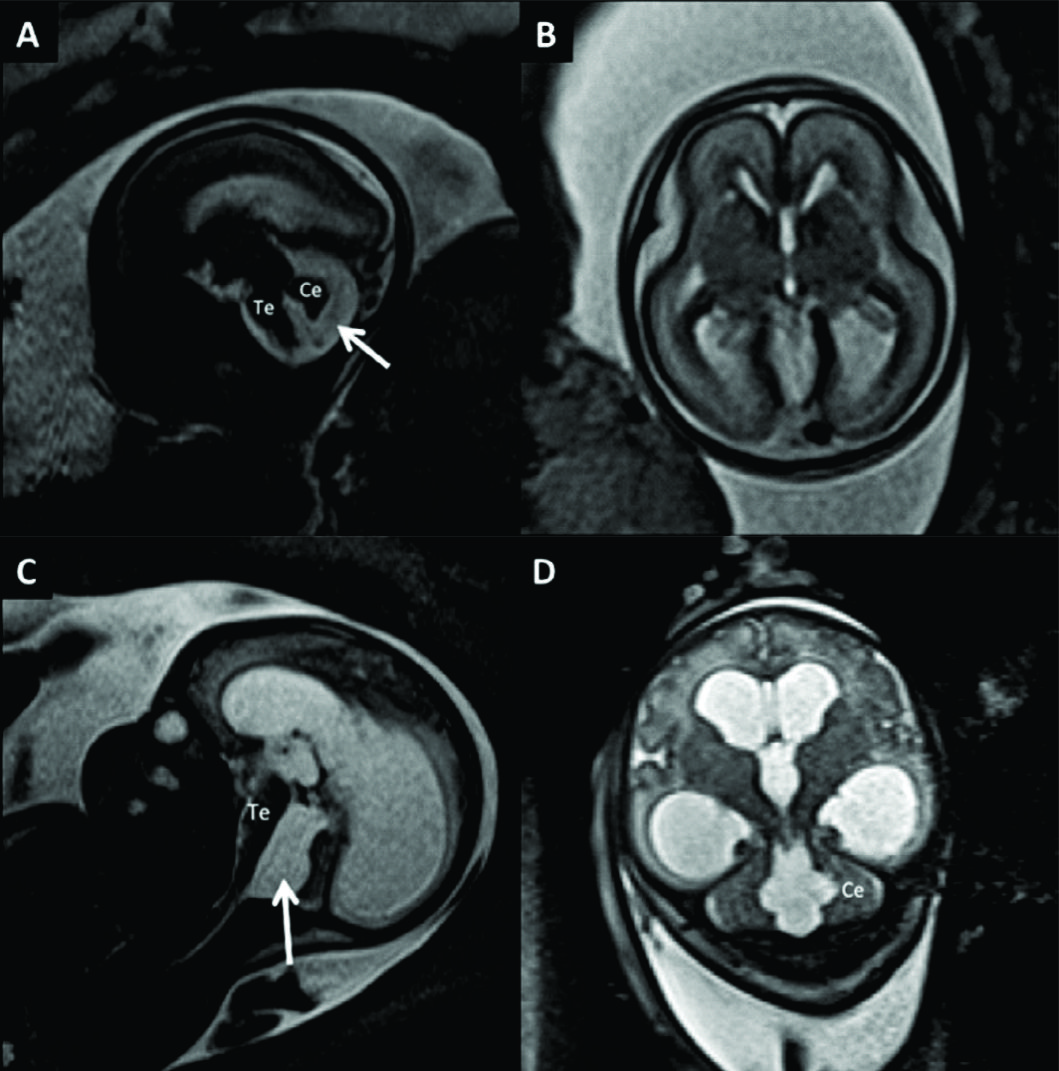

Figura 5

RM Fetal Hidranencefalia.

RMf a las 29 semanas de edad gestacional en paciente referido para confirmación de hidranencefalia, diagnóstico diferencial de HCF extrema. En A imagen sagital donde se observa la dilatación del sistema ventricular con estructuras de la fosa posterior de anatomía normal al igual que el IV ventrículo.

En B imagen coronal donde se observa la severa dilatación de los ventrículos laterales y se observan ambos tálamos (T) de aspecto normal con 3er ventrículo entre ellos.

En los cortes axiales (C y D) se observan los elementos ya destacados y además se corrobora otra estructura de línea media como la hoz cerebral (HC) y la presencia de escaso manto cerebral a nivel occipital (MC). Esto permite diferenciar esta entidad de las prosencefalias. Te: Tronco encefálico Ce: Cerebelo

Figura 6

RM Fetal Agenesia del Cuerpo Calloso.

Estudio realizado a las 27 semanas de edad gestacional con diagnóstico de agenesia del CC. En imagen sagital (A) no se observa el CC ni la cisura pericallosa. Los gyrus de la cara mesial toman un aspecto radiado como suele observarse en esta entidad. Los ventrículos laterales (è) toman un aspecto colpocefálico de dirección ántero posterior como se ve en el corte axial (B).

Las estructuras de la fosa posterior son normales. Te: Tronco encefálico Ce: Cerebelo